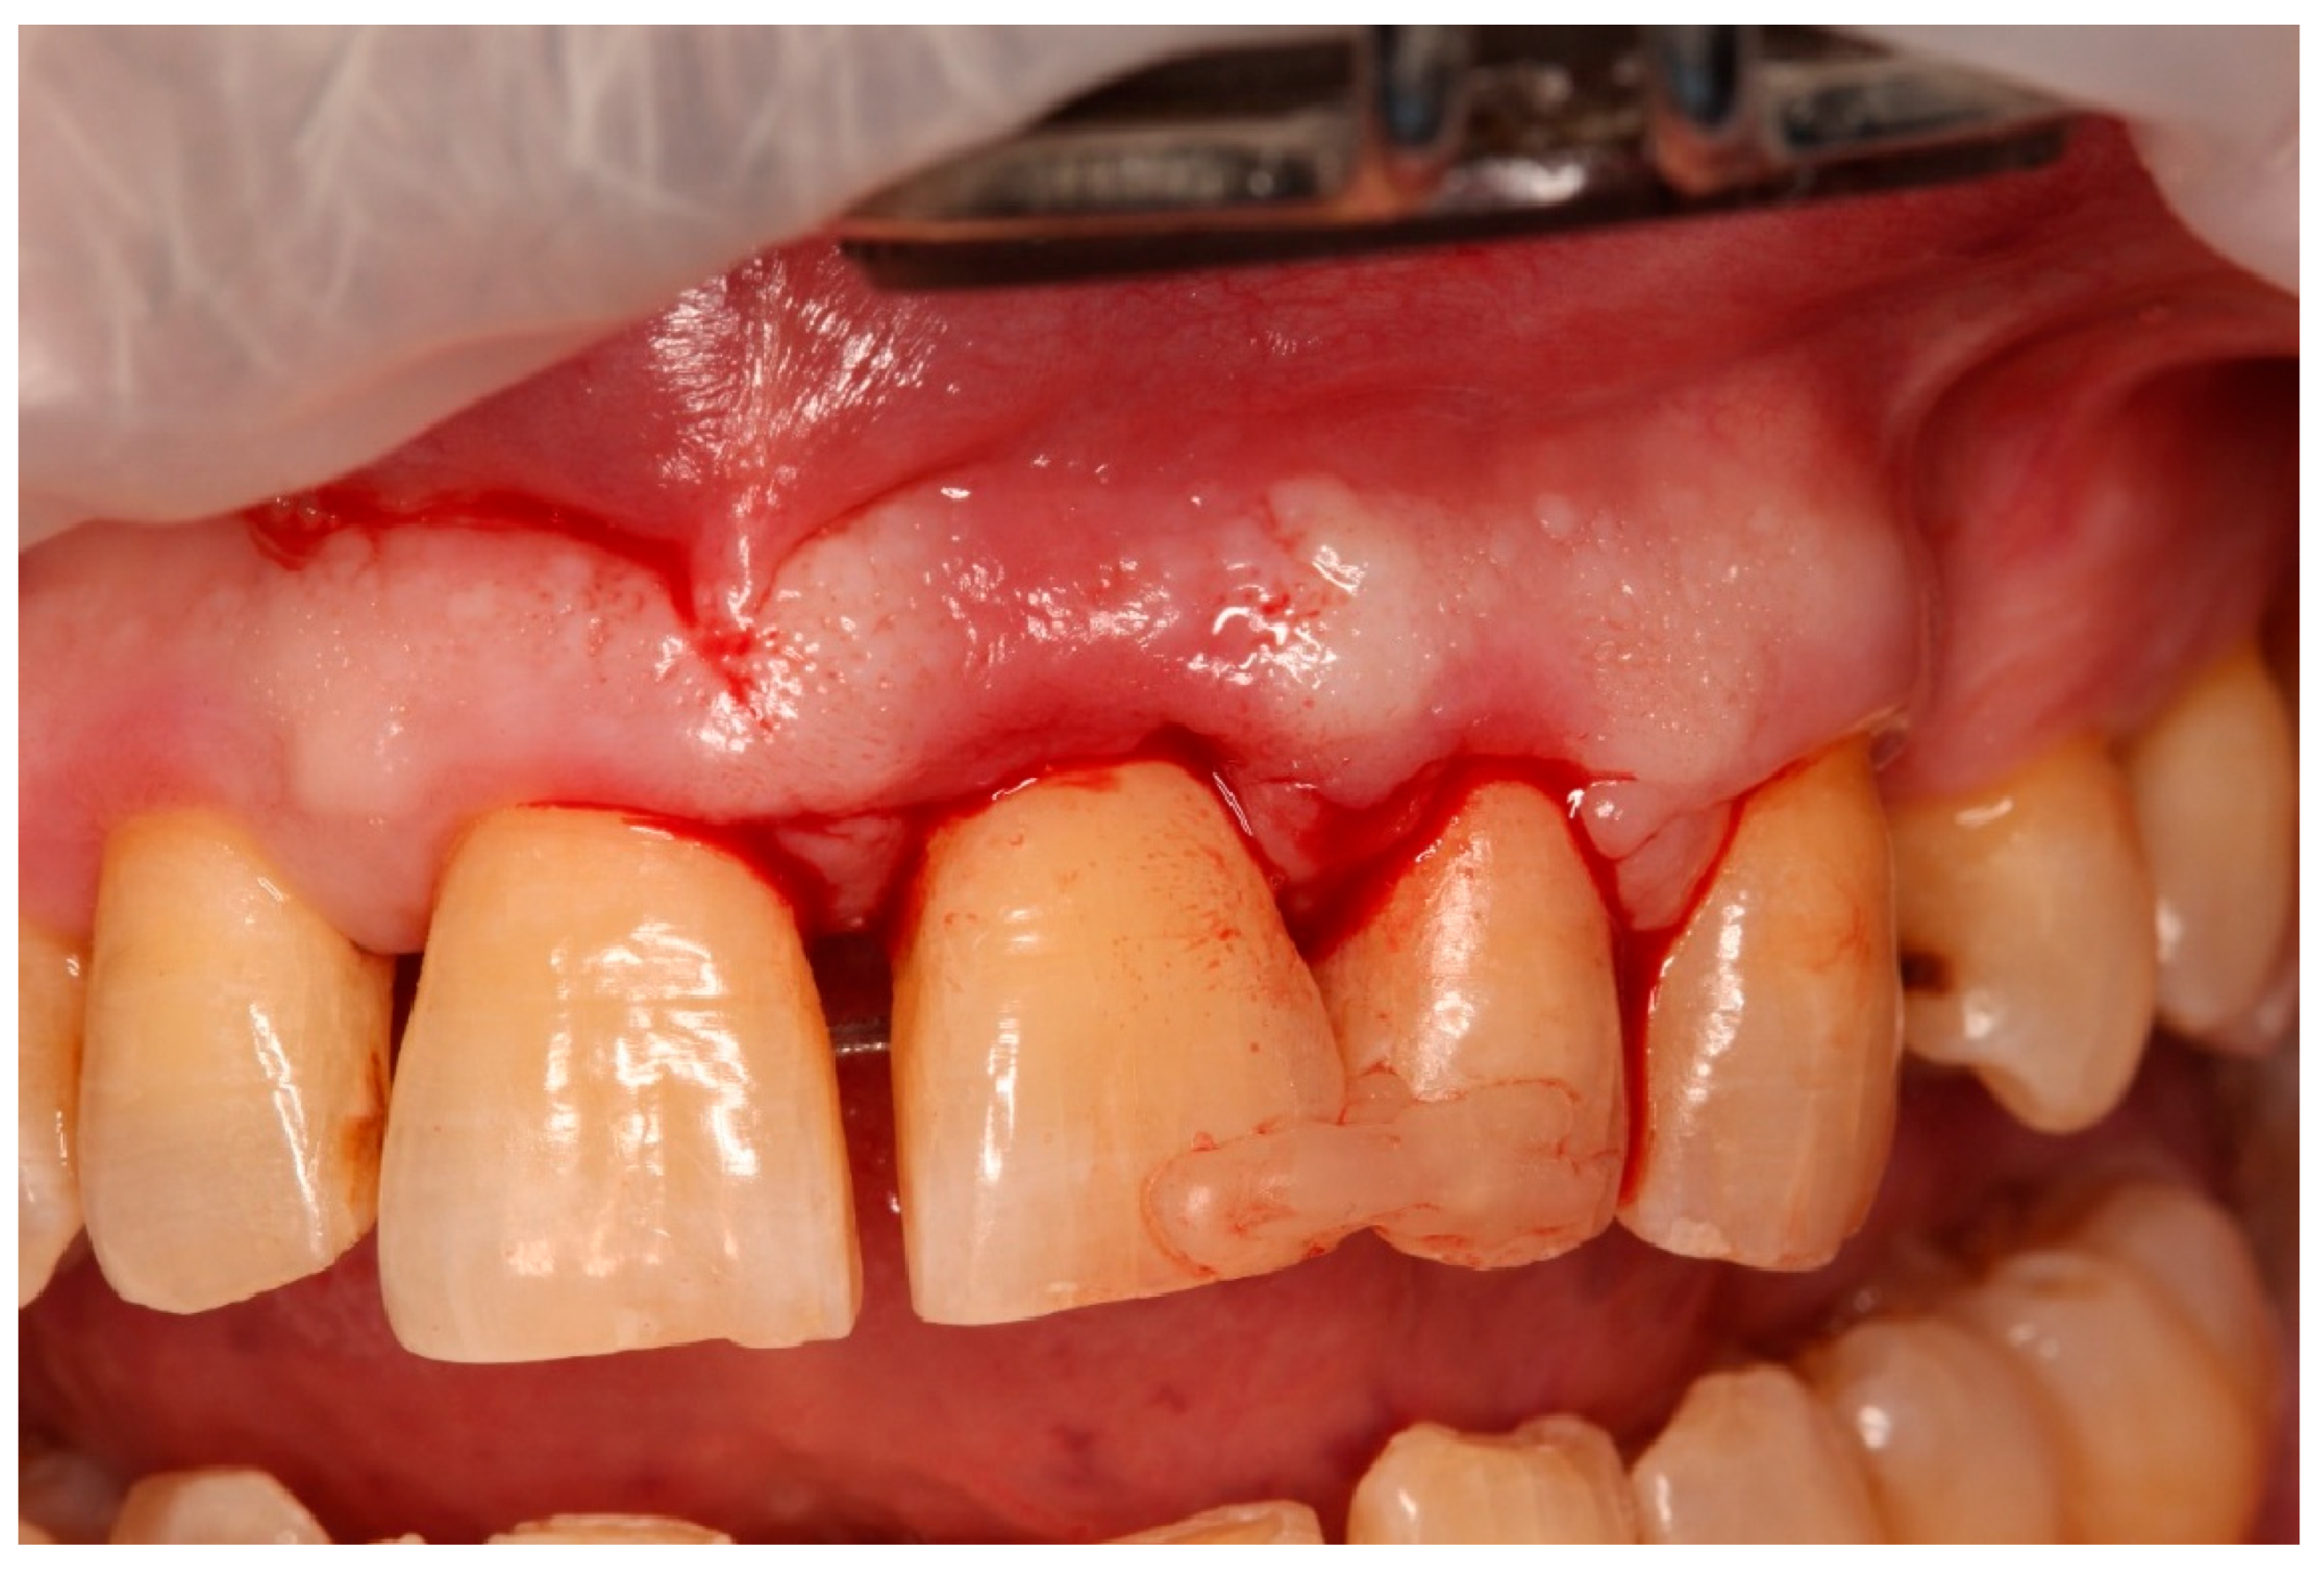

- Guided tissue regeneration: A full-thickness flap was elevated to expose the defect morphology. Autologous bone chips collected during drilling were combined with xenograft particles (Bio-Oss®, Geistlich Pharma, Wolhusen, Switzerland) and enamel matrix derivative (Emdogain®, Straumann, Basel, Switzerland) and placed around the replanted root. A resorbable collagen membrane (Bio-Gide®, Geistlich Pharma, Wolhusen, Switzerland) was positioned to stabilize the grafted area and support space maintenance. The flap was repositioned and sutured to achieve primary closure.